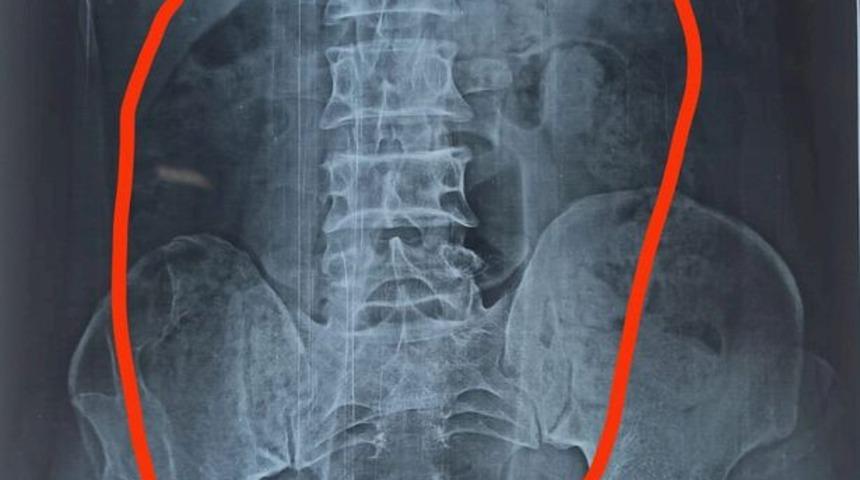

Hindistan’ın Madhya Pradesh eyaletindeki bir hastanede 55 yaşındaki bir hasta şiddetli mide ağrısı şikayetiyle acil servise başvurdu. Olayın nedenine ilişkin olarak çekilen röntgende adamın midesinde yabancı bir cismin bulunduğu tespit edildi. Büyük bir hızla ameliyata alınan adamın midesindeki 20 cm büyüklüğündeki plastik şişe cerrahi operasyonla çıkartıldı.

Uzman laparoskopik cerrah Manoj Chowdhary uzun saatler süren operasyonun ardından plastik şişeyi sağlam bir şekilde çıkartıldığını açıkladı. Ameliyatın ardından gözlem altında tutulan adamın operasyonuna ilişkin olarak hasta mahremiyeti koşulları nedeniyle ayrıntılara yer verilmedi.

Plastik şişenin hastanın midesinde bulunma nedeni ve yer alma şekline dair herhangi bir açıklama yapılmadı. Doktor hastayla yaptığı görüşmesinde 55 yaşındaki adamın “Oraya nasıl geldiğini bilmiyorum” ifadelerini kullandığını söyledi.